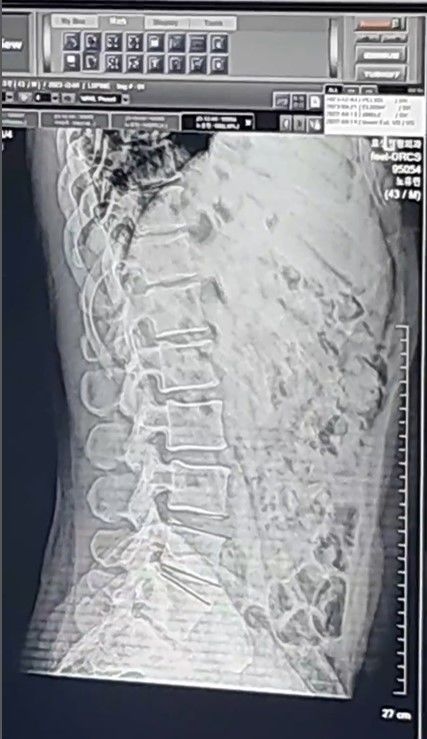

그리고 노유민의 아내는 4일, 그러니까 오늘 인스타그램에 노유민의 척추사진과 함께 그가 병원을 내원한 모습을 올렸다. 상황 설명도 덧붙여서!

“다행히 심각한 골절이나 척추손상은 없었고 디스크 충격 때문에 치료는 불가피하다고 해 주사맞고 물리치료받고 있다. 이만하길 천만다행이라는 안도감과 함께 엑스레이 사진마저도 너무 예뻐 보인다. 걱정해주시고 위로해주셔서 감사하다”고 덧붙였다.